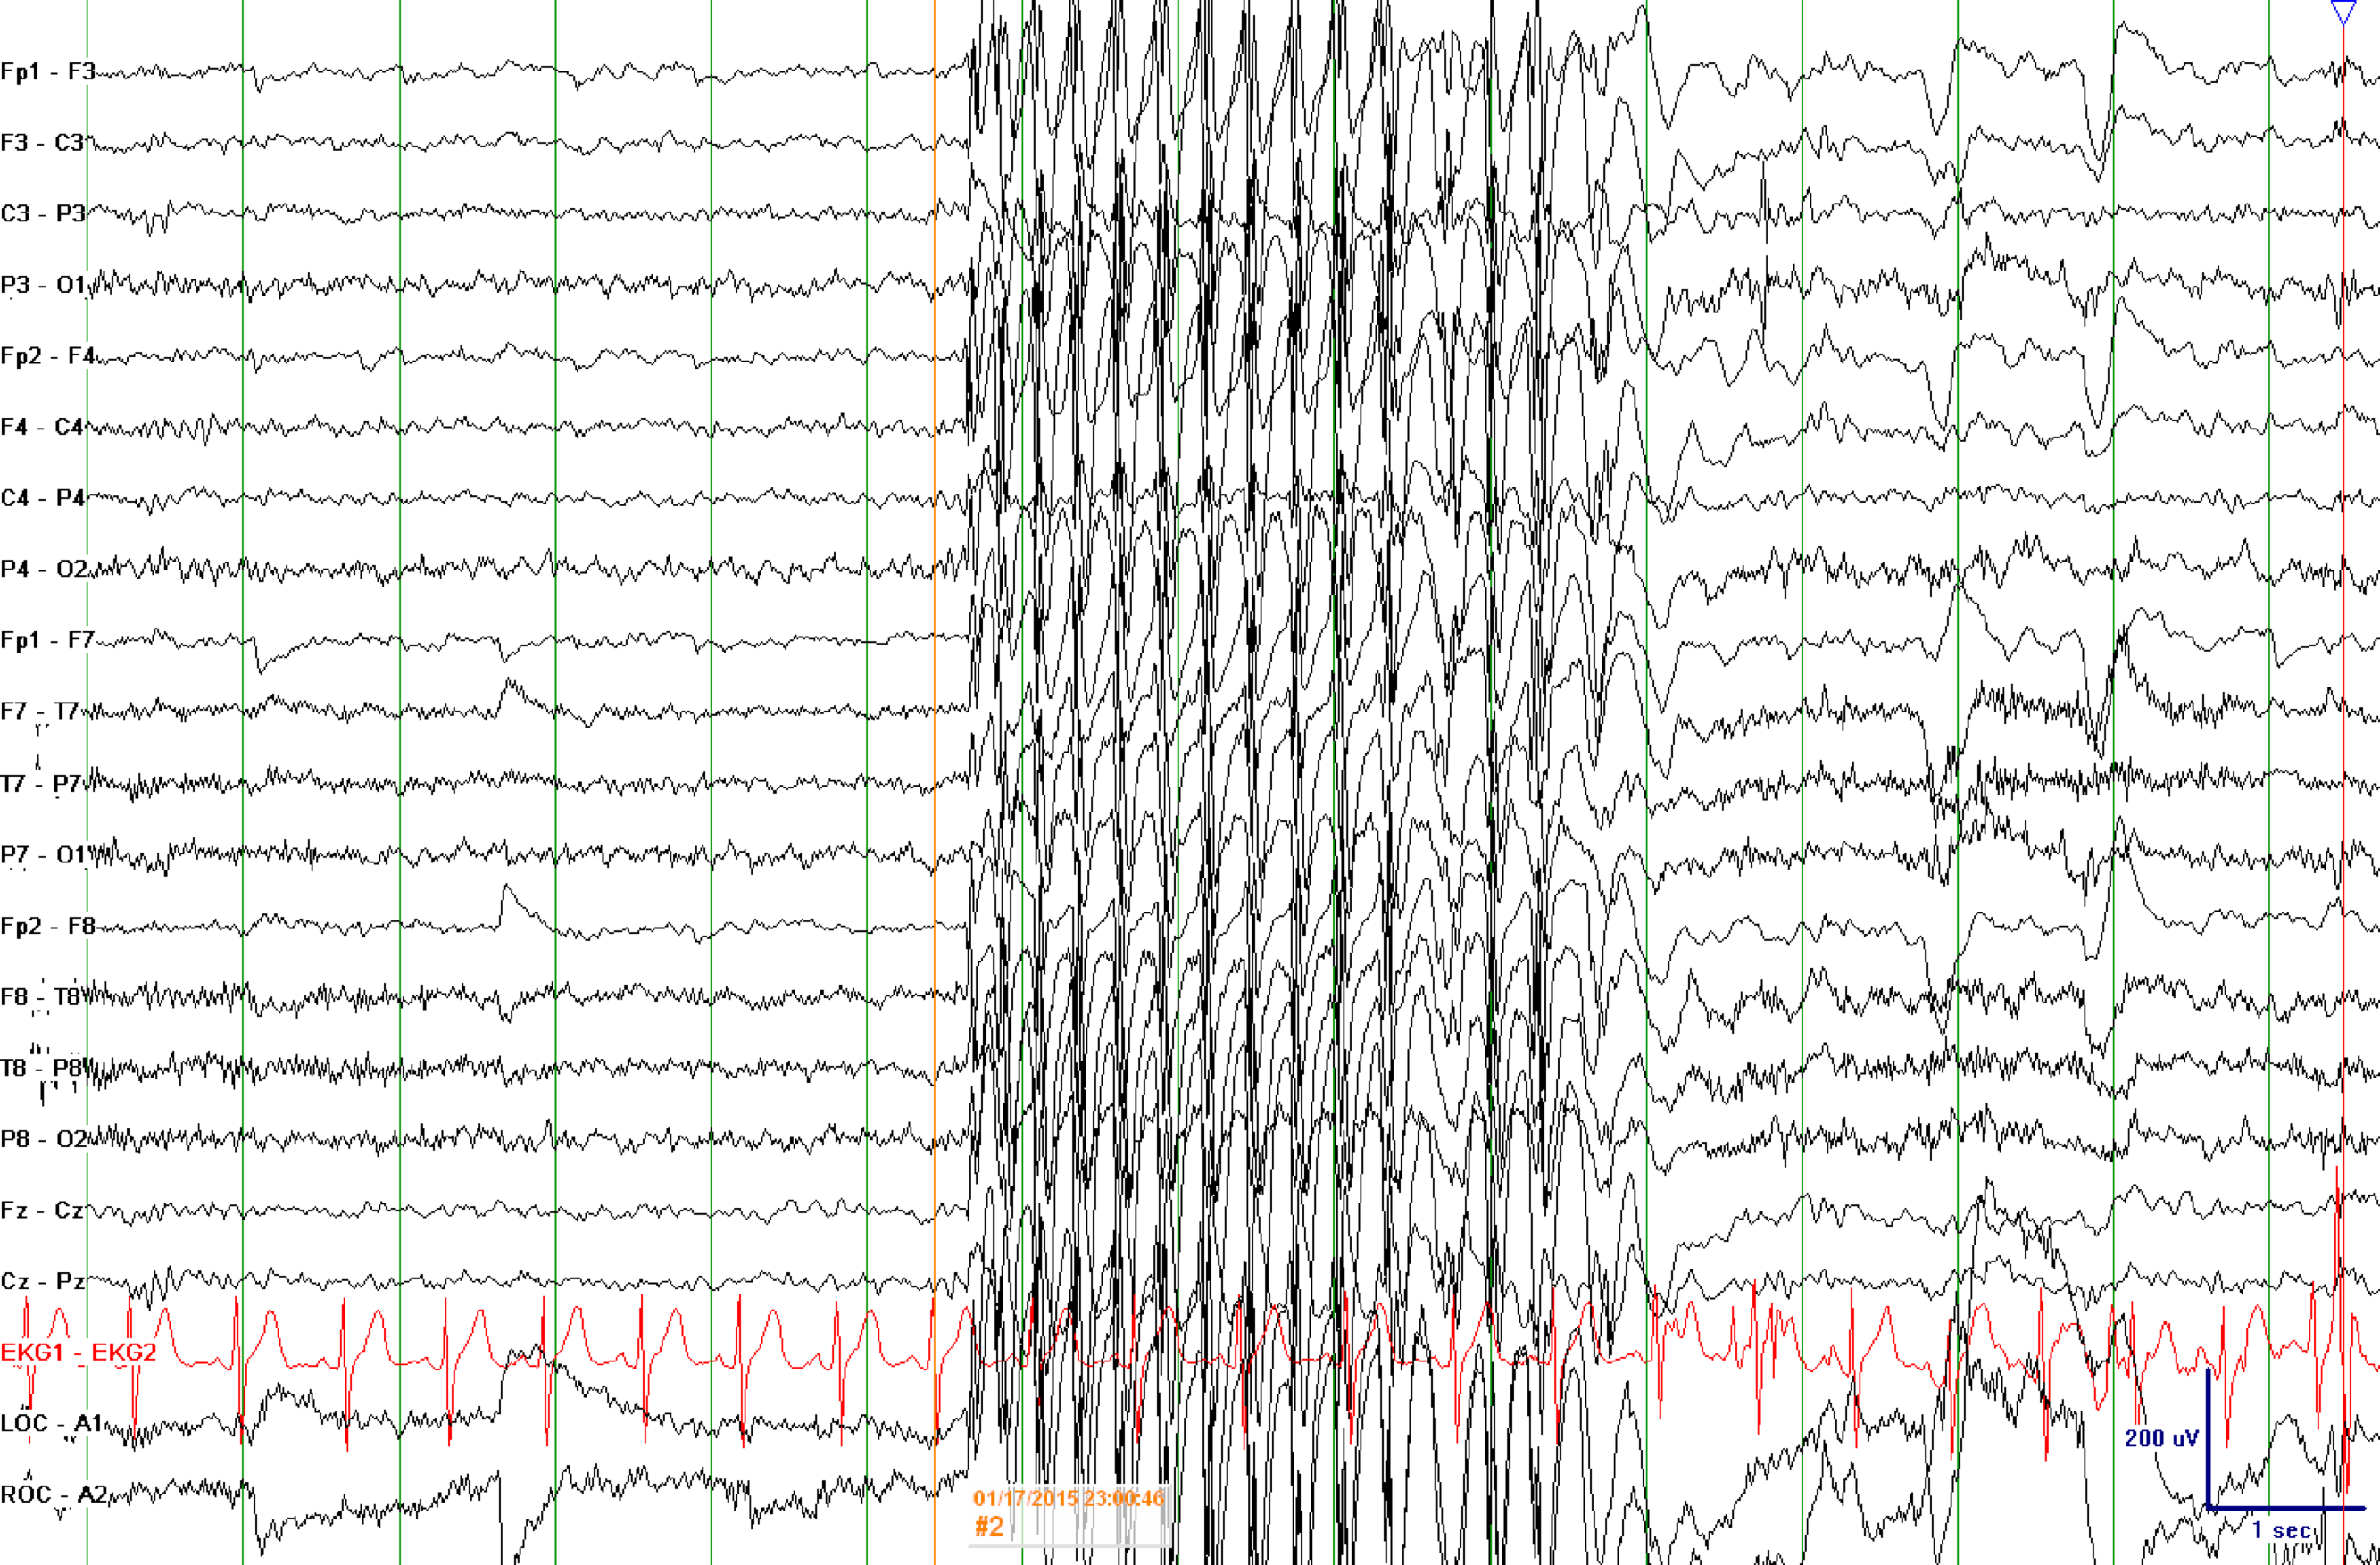

• An EEG (electroencephalogram) is done to look for possible seizure activity. Hyperventilation and photic stimulation (exposure to rapid flashing lights) are often performed during the EEG. The EEG shows generalized polyspike or spike and wave discharges at 3-4 Hz (cycles per second).

• The EEG shows spike and wave discharges at 3 to 6 Hz (cycles per second) that are generalized (the same on both sides of the brain).

EEG 3 To 6 1

EEG 3 To 6

Examples of 3 to 4 Hz generalized spike wave